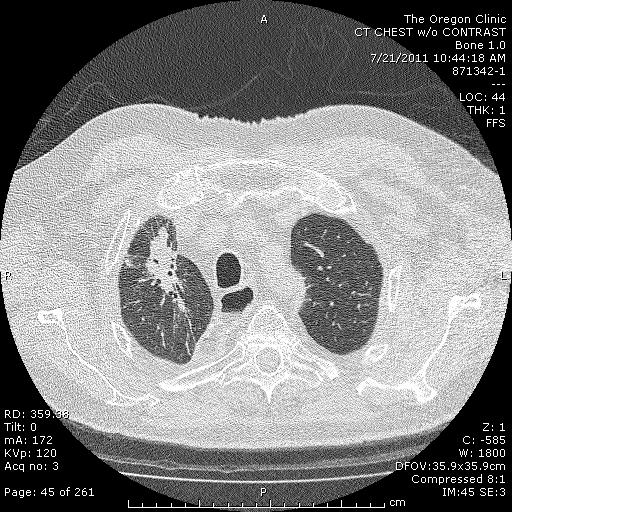

Tomografías computarizadas de pacientes con lesión pul- monar inducida por radiación ... |

... coinciden casi exactamente con las tomadas a pacientes infectados con la enfermedad del coronavirus COVID-19 |